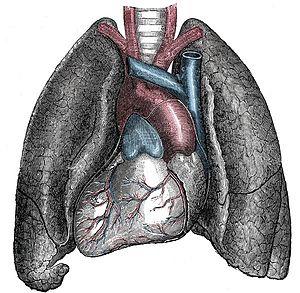

| Situs inversus causes the positions of the heart and lungs to be mirrored. | |

Effect on anatomy

The condition affects all major structures within the thorax and abdomen. Generally, the organs are simply transposed through the sagittal plane. The heart is located on the right side of the thorax, the stomach and spleen on the right side of the abdomen and the liver and gall bladder on the left side. The heart's normal right atrium occurs on the left, and the left atrium is on the right. The lung anatomy is reversed and the left lung has three lobes while the right lung has two lobes. The intestines and other internal structures are also reversed from the normal, and the blood vessels, nerves, and lymphatics are also transposed.

If the heart is swapped to the right side of the thorax, it is known as "situs inversus with dextrocardia" or "situs inversus totalis". If the heart remains on the normal left side of the thorax, a much rarer condition (1 in 2,000,000 of the general population), it is known as "situs inversus with levocardia" or "situs inversus incompletus".